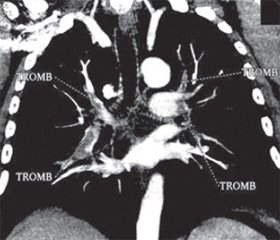

Для окончательной верификации диагноза (так как состояние пациента оставалось гемодинамически стабильным) была проведена мультиспиральная компьютерная томография (МсКТ), которая подтвердила наличие ТЭЛА и выявила множественные тромбы в основных ветвях обеих легочных артерий (рис. 3, МсКТ при поступлении).

С учетом клинической картины заболевания (нормальные параметры центральной гемодинамики), данных инструментальных (признаки дисфункции ПЖ) и лабораторных (повышение уровня тропонина) методов исследования данная ТЭЛА была классифицирована как субмассивная, или промежуточного риска [1, 7]. В то же время наличие одышечного (SpO2 — 87 %) и болевого синдромов, массивность тромботической закупорки основных ветвей легочной артерии, выраженная степень дисфункции ПЖ, а также отсутствие видимых факторов риска развития кровотечений явились основанием для проведения тромболитической терапии (ТЛТ). ТЛТ проводилась альтеплазой в дозе 100 мг в течение 2 часов. Во время проведения ТЛТ отмечалась кровоточивость десен, которую удалось остановить полосканием полости рта раствором аминокапроновой кислоты. Других кровотечений не было. Через 12 часов после окончания ТЛТ состояние пациента существенно улучшилось, боли в грудной клетке и одышка прекратились. Насыщение артериальной крови кислородом при пульсоксиметрии (SpO2) возросло до 96 % (дыхание воздухом), ЧСС снизилась до 70 ударов в 1 минуту. Повторная ЭхоКГ выявила существенное уменьшение размеров и перегрузки ПЖ, снижение степени легочной гипертензии (рис. 2, ЭхоКГ после проведения ТЛТ). Контрольная мультиспиральная КТ, проведенная на 5-е сутки после ТЛТ (рис. 3), выявила значительное улучшение легочного кровотока с наличием единичных тромбов в субсегментарных ветвях легочной артерии. При компрессионной сонографии вен нижних конечностей тромбы в глубоких венах нижних конечностей не выявлены (признаки посттромбофлебитической болезни). Пациент был переведен на длительный прием пероральных антикоагулянтов и выписан в удовлетворительном состоянии. ЭКГ при выписке представлено на рис. 4.